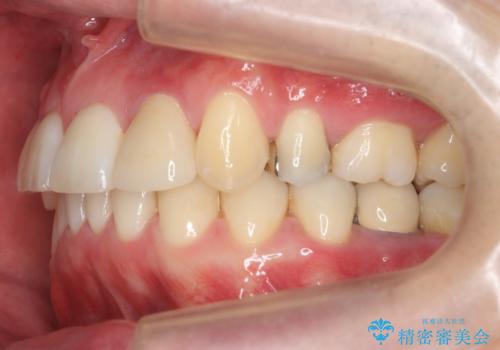

下の歯がないところに、奥歯が倒れこんでいたため、矯正治療で倒れこんだ歯を起こして、インプラントを植立しました。

- 197万円 (矯正治療95万円、インプラント治療72万円(下顎両側6)、その他補綴治療30万円(上顎両側2))費用は治療当時の料金となります